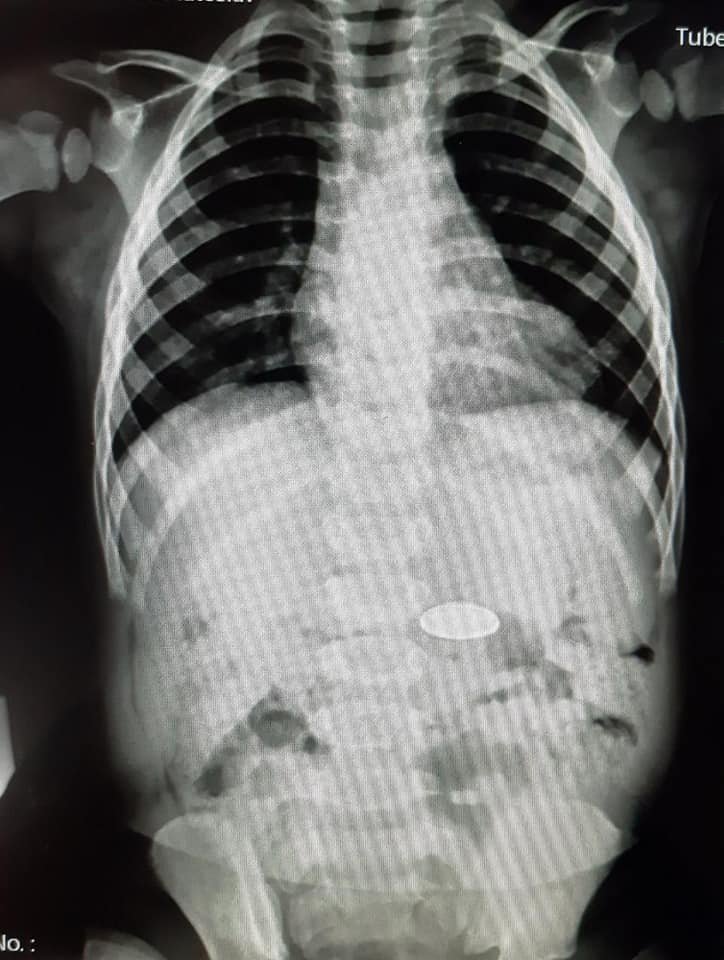

"Ребенок проглотил металлический значок. За врачебной помощью родители не обращались, занимались самолечением. Состояние не улучшилось, обратились к ОДКБ. На осмотре жалобы отсутствуют", - написал медик. Врачи достали инородный предмет и дали семье рекомендации. Сейчас ребенок в порядке.